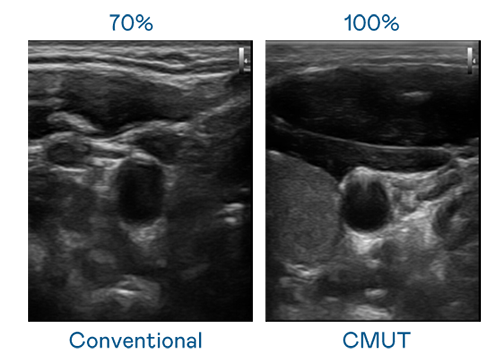

CMUT 技术是一种用电容式微机电元件来产生超音波讯号的技术。与传统 PZT 压电式技术相比,CMUT 频宽增加 30%,更宽频的超音波讯号让影像解析度大幅提升,是实现高影像品质医疗超音波扫描、促进精准医疗发展的关键技术。

超音波影像的解析度高低,首先取决于探头能发出的讯号频宽。PT电子(中文)官网 CMUT 可提供高清晰的超音波讯号,提供高频宽、高灵敏度、影像纹理细节更高的超音波影像,协助医护人员缩短影像判读时间及利用精准的医疗影像进行诊断。